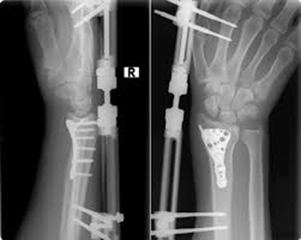

Tedavi YöntemleriEl bileği burkulmasının tedavisi, yaralanmanın şiddetine bağlı olarak değişiklik göstermektedir. Tedavi yöntemleri genellikle aşağıdaki gibidir:

İyileşme SüreciEl bileği burkulması sonrası iyileşme süreci, yaralanmanın ciddiyetine ve uygulanan tedavi yöntemlerine bağlı olarak değişir. Genellikle hafif burkulmalar birkaç gün içinde iyileşirken, daha ciddi yaralanmaların tamamen iyileşmesi haftalar alabilir. Bu süreçte hasta, doktorun önerilerine uymalı ve bileğini fazla zorlamamalıdır. SonuçEl bileği burkulması, günlük yaşamı etkileyen yaygın bir yaralanmadır. Belirtilerinin farkında olmak ve tedavi yöntemlerine başvurmak, iyileşme sürecini hızlandırabilir. Bu yaralanmadan kaçınmak için spor yaparken uygun tekniklerin kullanılması ve koruyucu ekipmanların giyilmesi önerilmektedir. Eğer belirtiler uzun süre devam ederse veya ağrı dayanılmaz hale gelirse, mutlaka bir sağlık profesyoneline başvurulmalıdır. |